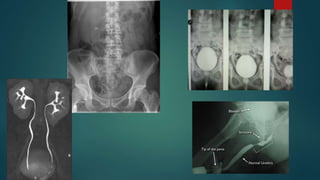

 30 year old male right flank

pain; ultrasound shows proximal

hydroureter and mild

hydronephrosis

 Scout- apparently normal with

no evidence of calculus

 10 min film- right sided proximal

hydroureter and mild dilatation of

pelvicalyceal system

 15 min film- findings are persistent and

a filling defect is noted at the L3-L4

level